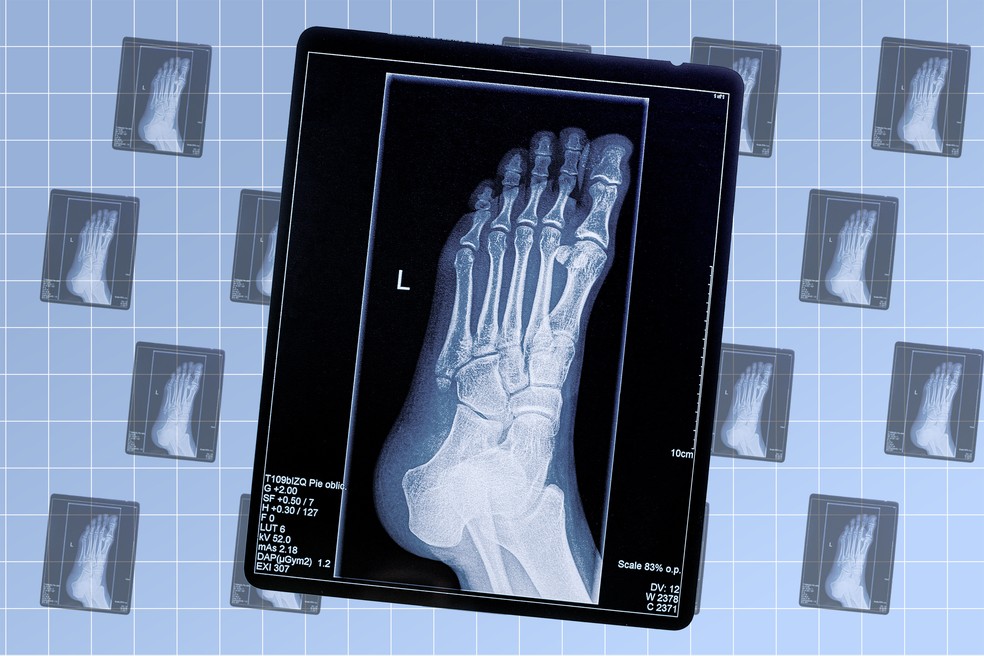

Raio-x — Foto: Arte EN

Cerca de 3,6 bilhões de exames de diagnósticos por imagem são realizados globalmente a cada ano, de acordo com a Organização Mundial da Saúde (OMS). E entre eles o raio-X ainda é a modalidade mais comum.

Essa tecnologia, que utiliza radiação eletromagnética de alta energia para visualizar estruturas internas do corpo, foi descoberta em 8 de novembro de 1895 pelo físico alemão Wilhelm Conrad Röntgen (1845–1923), na época em que era professor da Universidade de Würzburg.

O impacto do raio-x foi imediato, pois, pela primeira vez, médicos podiam enxergar o interior do corpo humano sem a necessidade de abri-lo, transformando assim a relação entre diagnóstico e tratamento.

Além disso, com o desenvolvimento da tecnologia, hoje os equipamentos utilizam doses significativamente menores de radiação. Fora que são digitais e produzem imagens de altíssima resolução.